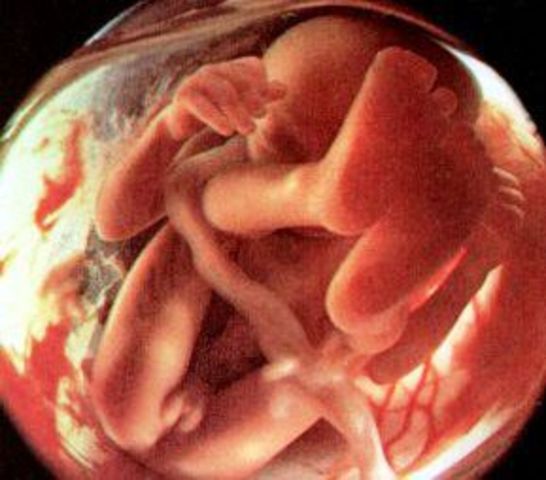

El producto ya puede oír, es más activo y continua moviéndose y flotando, la madre siente una agitación en la parte inferior del abdomen, esto recibe el nombre de primer movimiento fetal; al finalizar de esta etapa el puede tragar.

al finalizar el quinto mes el producto mide de 25 a 30 cm y pesa entre 225 a 500 gr; su cuerpo esta cubierto de vernix caseosa que es una capara de rasa producida por las glándulas sebáceas.